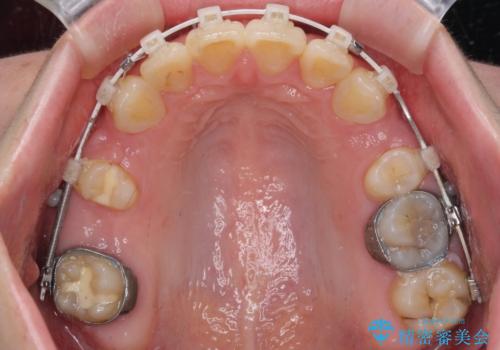

- 矯正装置

- 審美装置

上顎前突を改善するために上顎左右第一小臼歯を抜歯し、補助装置を用いて上顎臼歯が前方に移動しないように工夫しながら、表側のワイヤー装置にて歯列を整えていくこととしました。